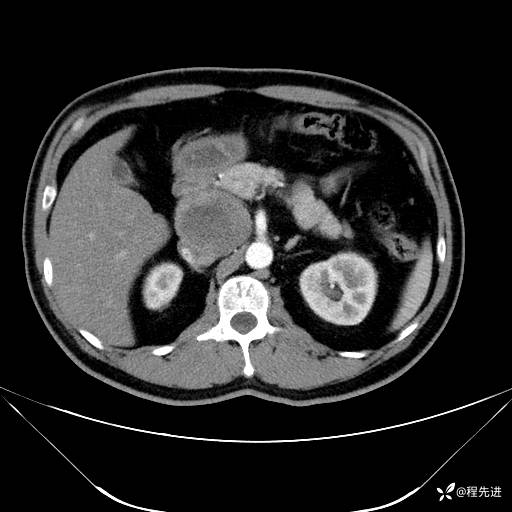

【腹盆】特别精彩病例|发现腹膜后肿物1月余

患者年龄:42岁

主诉:发现腹膜后肿物1月余

现病史:患者1月余前查体,行超声检查提示:后腹膜囊实性肿块;慢性胆囊炎伴胆囊内结石;无腹痛腹胀,不伴腹泻发热等;偶感腰背部酸痛。

CT平扫+增强: